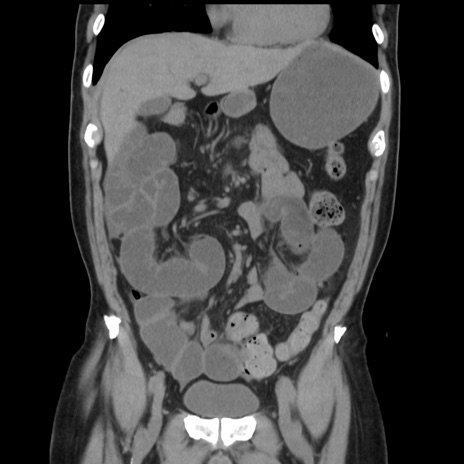

症例16(冠状断像)

【症例】 70歳代男性

【主訴】 腹痛、嘔吐

【現病歴】 約1ヶ月前より間欠的に腹痛と嘔吐あり、当院消化器内科を受診したところCTで多発する肝臓のLDAを指摘され、精査中であった。以降は消化器症状は安定していたが、2日前より嘔気と腹痛があり、同日より排便・排ガスが消失した。改善認めず、 本日、救急外来を受診した。

【既往歴】 大腸ポリープ切除後。

【身体所見】意識清明・会話良好、BT 36.3℃、BP 127/80mmHg、 P 80bpm、腹部:膨満あり、平坦・軟、上腹部正中および下腹部正中に圧痛あり、反跳痛なし、筋性防御なし。

【データ】WBC 7200、CRP 0.77

横断像